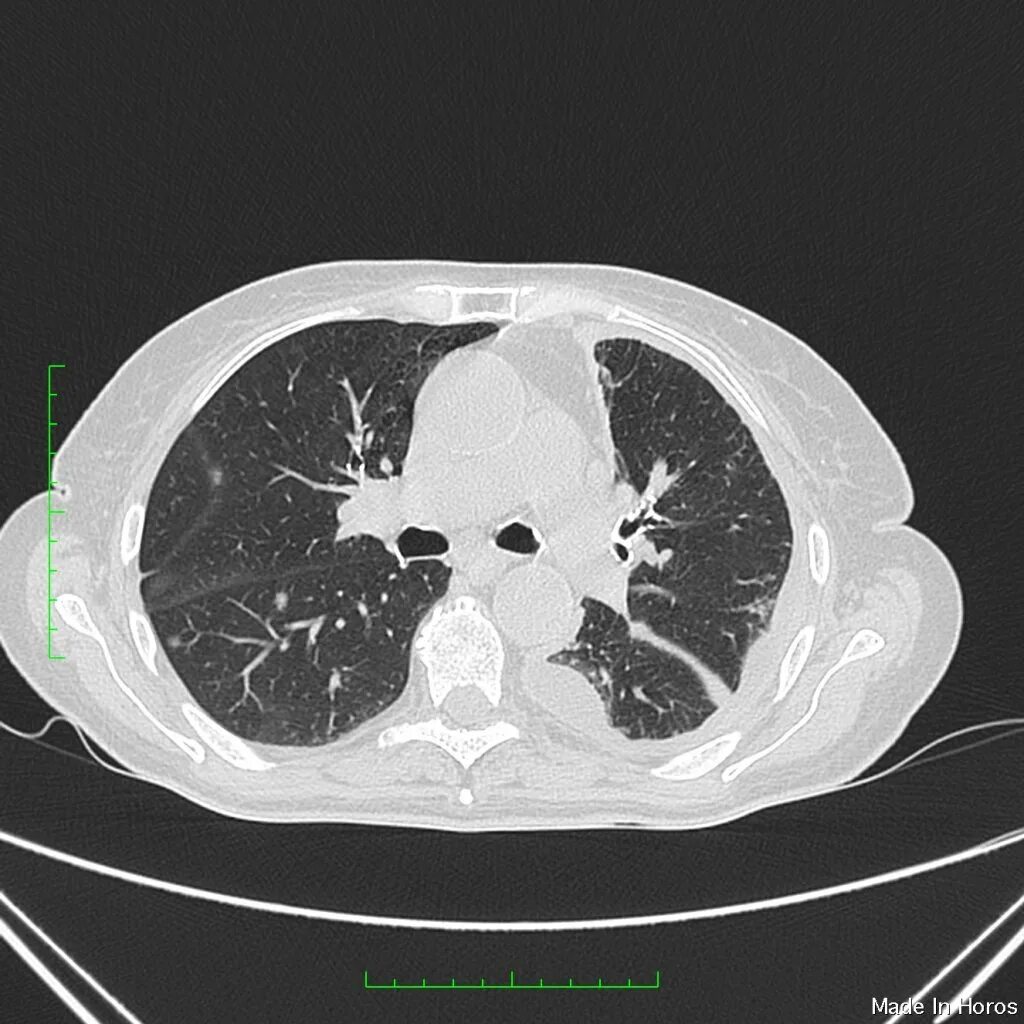

Метастазы плевры